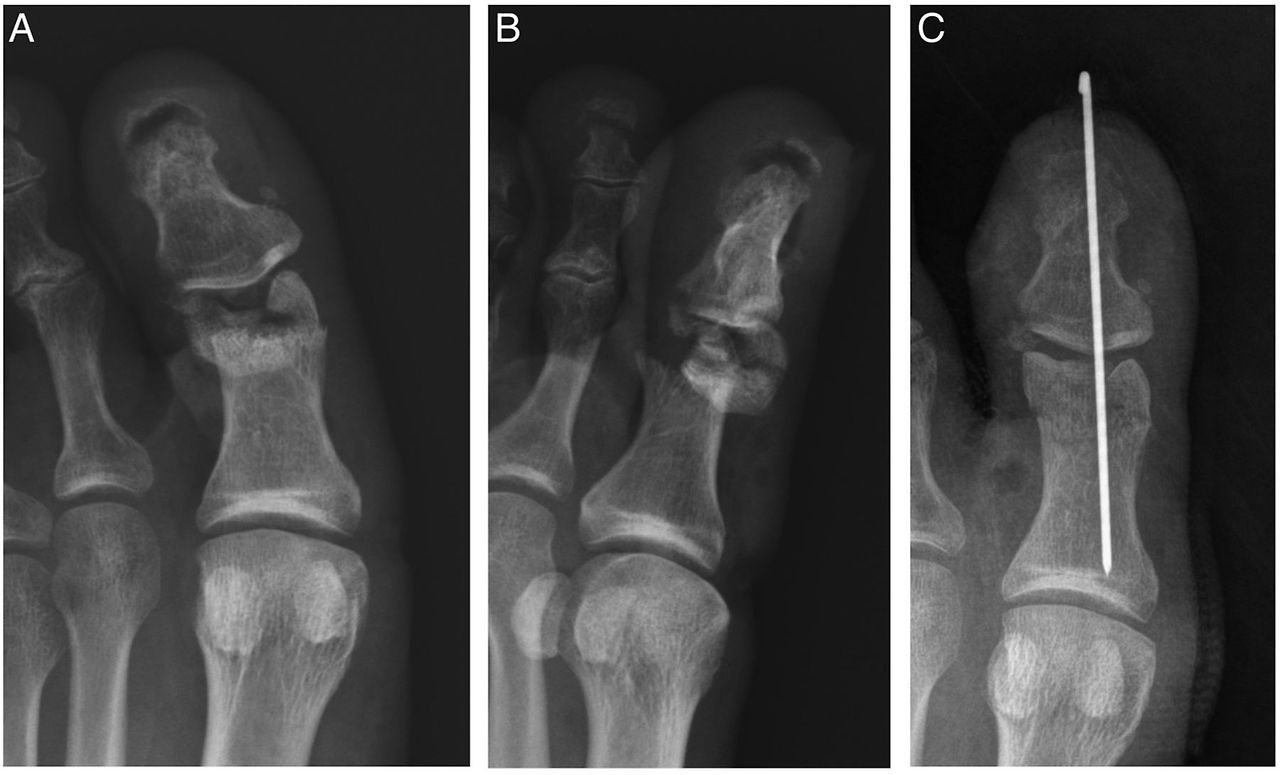

발가락 골절 수술

복합 골절이나 압박 골절의 경우 수술이 필요할 수 있습니다. 발가락 골절 수술 후 추가로 2-4주의 회복 기간이 필요하며, 비용은 60-150만원 정도로 다양합니다. 수술 방법에는 핀을 박는 방법과 금속판을 사용하는 방법이 있습니다.